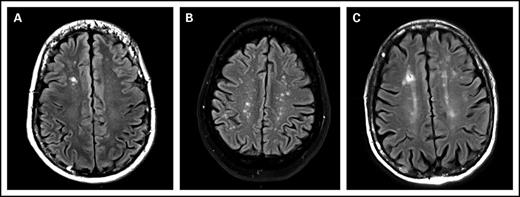

The prevalence of WMCs in the 83 included patients was 49% (95% confidence interval, 39%-60%). ARWMC score was calculated for these 41 patients. The ARWMC score was 1 in 15 patients, 2 to 4 in 12 patients, and 5 or greater in 12 patients. The lesions were focal in 49% (20/41) of patients, and the remaining patients had either lesions in several distinct brain areas or several lesions in a single area that were beginning to become confluent. None of the patients had more severe lesions. WMCs were localized to the frontal area in 32 (78%) of 41 patients, the parieto-occipital area in 19 (46%) of 41 patients, the temporal area in 3 (7%) of 41 patients, the basal ganglion region in 7 (17%) of 41 patients, and the infratentorial area in 3 (7%) of 41 patients (Figure 1).

MRI, FLAIR images, axial slices. (A) White matter lesion, type 1: focal lesion. Focal hypersignal on right frontal lobe. (B) White matter lesion, type 2: beginning confluence lesion. Multiple focal hypersignal on right and left hemispheres. (C) Another white matter lesion, type 2: beginning confluence lesion. Multiple hypersignal on right and left hemispheres with small confluence.